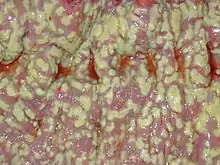

| Pathological specimen showing pseudomembranous colitis | |